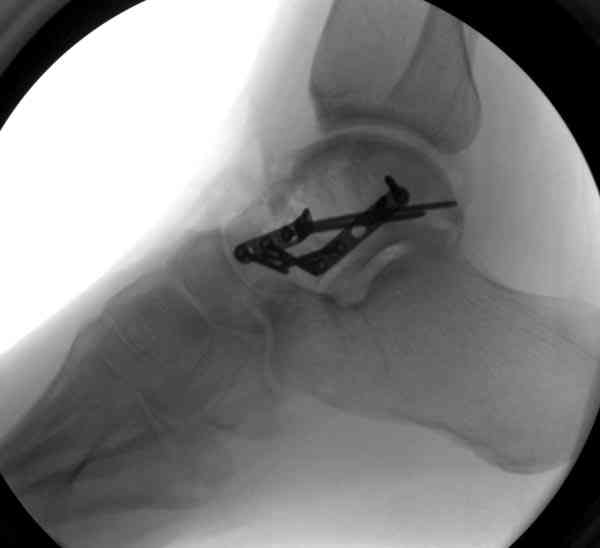

При в первом типе придерживаемся закрытой репозиции, а у всех остальных в зависимости от смещения предпочитаем открытую репозицию, фиксация шурупами или пластиной. Пластина 2.4 мм более предпочтительна для удержания мелких костных осколков.

В вашем случае доступ через перелом медиальной лодыжки, обычный доступ через остеотомии лодыжки, где имеется возможность прямой репозиции тарана, после фиксации шурупами, лодыжки фиксируются обычным 2х лодыжечным методом.

Случай с множественным оскольчатым переломом тарана оперированный из двойного доступа.

Через 2 мес.:

Два фрагмента суставной поверхности тарана можно восстановить боковой компрессией шурупами и дополнительно костная пластика.

(кстати, на нашем случае была применена костная пластика-allograft crouton для заполнения дефектов)